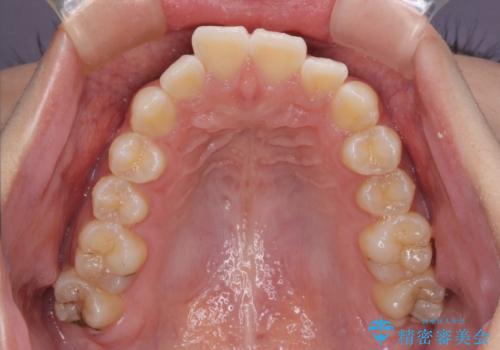

上下前歯の突出感とデコボコを気にして来院された患者様です。

インビザラインによる上下歯列の側方拡大と後方移動、必要に応じてIPR(歯と歯の間を削る)によりスペースの獲得により歯列を整えることとしました。

治療途中、出産や転居があり、2年ほど治療期間が長くなってしまいましたが、前歯の歯並びや飛び出した感覚を無事に改善させることができました。